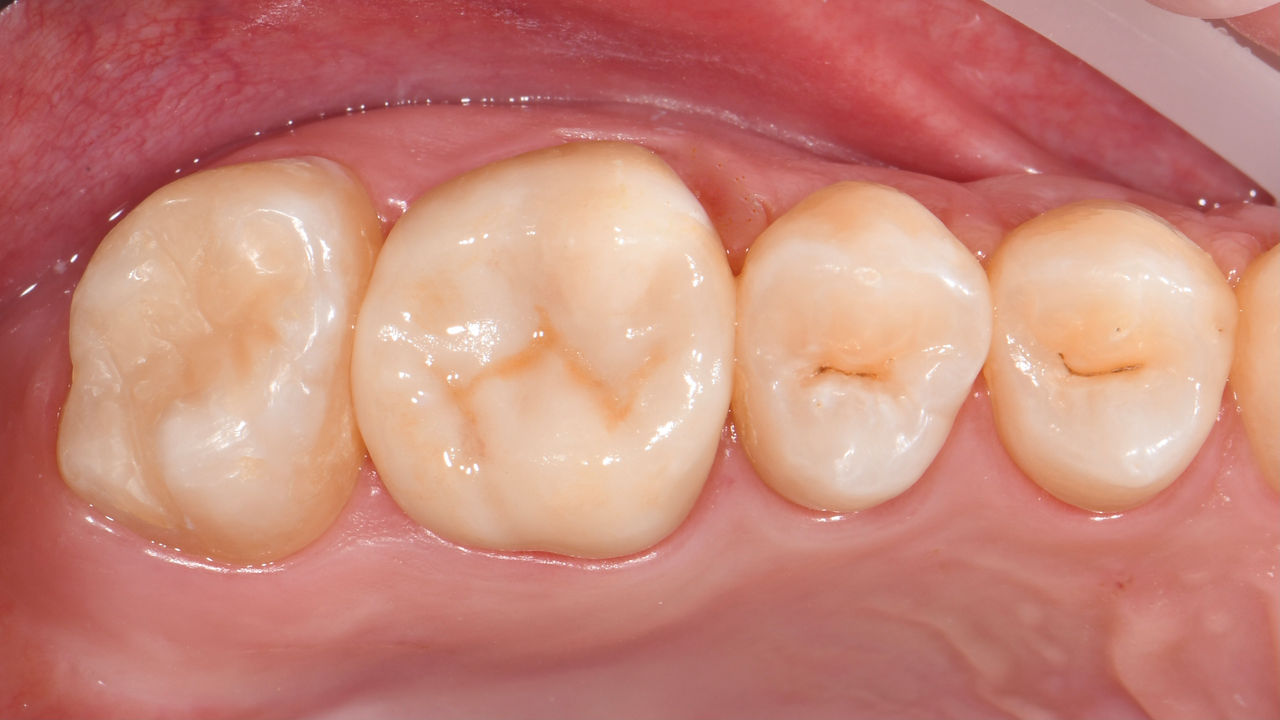

Restauration de la deuxième molaire mandibulaire en consultation

Couronne partielle CEREC Tessera

Une deuxième molaire mandibulaire sensible présentait des fissures ainsi qu’une restauration composite de classe I étendue sur la face vestibulaire. Conformément au concept mini-invasif, une couronne partielle CFAO a été planifiée, fabriquée et collée à l’aide du CEREC Tessera en une seule visite.

Avant : Restauration en amalgame défaillante nécessitant un remplacement. Patient se plaignant de sensibilité et dent présentant de multiples fissures.

Après : Restauration d’une couronne partielle CFAO réalisée en consultation avec la vitrocéramique CEREC Tessera Advanced Lithium-Disilicate.